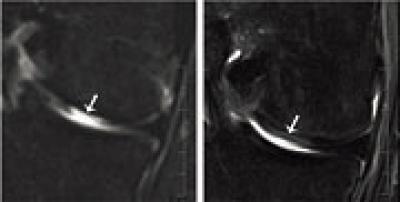

Cartilage cells from the nasal septum (nasal chondrocytes) have a distinct capacity to generate a new cartilage tissue after their expansion in culture. In an ongoing clinical study, the researchers have so far taken small biopsies (6 millimeters in diameter) from the nasal septum from seven out of 25 patients below the age of 55 years and then isolated the cartilage cells. They cultured and multiplied the cells and then applied them to a scaffold in order to engineer a cartilage graft the size of 30 x 40 millimeters. A few weeks later they removed the damaged cartilage tissue of the patients' knees and replaced it with the engineered and tailored tissue from the nose. In a previous clinical study conducted in cooperation with plastic surgeons and using the same method, the researchers from Basel recently already successfully reconstructed nasal wings affected by tumors.

The scientists around first author Dr. Karoliina Pelttari were especially surprised by the fact that in the animal model with goats, the implanted nasal cartilage cells were compatible with the knee joint profile; even though, the two cell types have different origins. During the embryonic development, nasal septum cells develop from the neuroectodermal germ layer, which also forms the nervous system; their self-renewal capacity is attributed to their lack of expression of some homeobox (HOX) genes. In contrast, these HOX genes are expressed in articular cartilage cells that are formed in the mesodermal germ layer of the embryo.